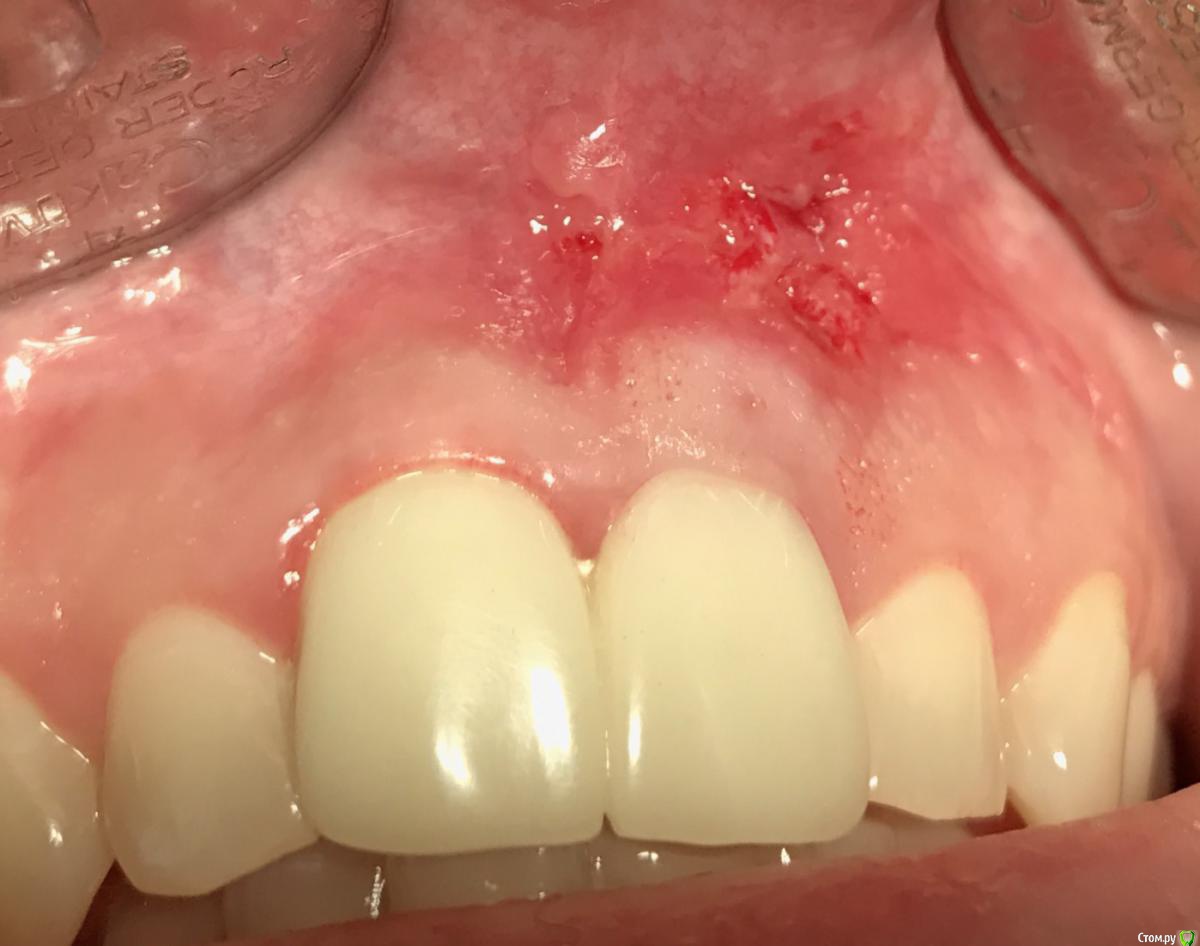

Astronaft Опубликовано 22 июня, 2018 Поделиться Опубликовано 22 июня, 2018 Коллеги, нужен ваш совет как поступить.Девушка, молодая, высокая улыбка , много десны видно.Появился свищь 5мм выше зенитов 11,12.11 - на удаление.http://miworks.weebly.com/uploads/1/6/8/7/16879370/untitled-1_1_orig.jpg http://miworks.weebly.com/uploads/1/6/8/7/16879370/x06408-1_orig.jpghttp://miworks.weebly.com/uploads/1/6/8/7/16879370/1_1_orig.jpg План: удалить, одномоментно имплант с времянкой, десну с бугра. БиоОсс вестибулярно.Мучает сомнение накрывать мембраной или нет. Если мембрана надо отслаиваться. А тут 12-11 сосочек только держится на связках. А если не накрывать чего ожидать?Делитесь мнением. Спасибо.Планируем повышать зениты, что бы как-то обыграть ситуацию.http://miworks.weebly.com/uploads/1/6/8/7/16879370/3_1_orig.jpg Ссылка на комментарий

Jurai Опубликовано 22 июня, 2018 Поделиться Опубликовано 22 июня, 2018 Свищ есть - кортикальной нет. Одномоментно да с нагрузкой и без отслаивания - не самый лучший вариант. 6 Ссылка на комментарий

Astronaft Опубликовано 22 июня, 2018 Автор Поделиться Опубликовано 22 июня, 2018 У меня следующие размышления.1. Без времянки никак.2. Если резать - сосочек сразу затупится и укоротится. Я готов туннель сделать от клыка и прибить мембрану пином - лишь бы не резать. Биоосс мне нравится тем что будет держать обьем пару десятков лет, выступая в роли щита. Даже если кость не вырастет, все равно гранулы будут держать десну.Хочу имплант заглубить на 3 мм от медиальной кортикалки. При этом имплант со стороны 12 будет на 2 мм не в кости.http://miworks.weebly.com/uploads/1/6/8/7/16879370/2_5_orig.jpg Ссылка на комментарий